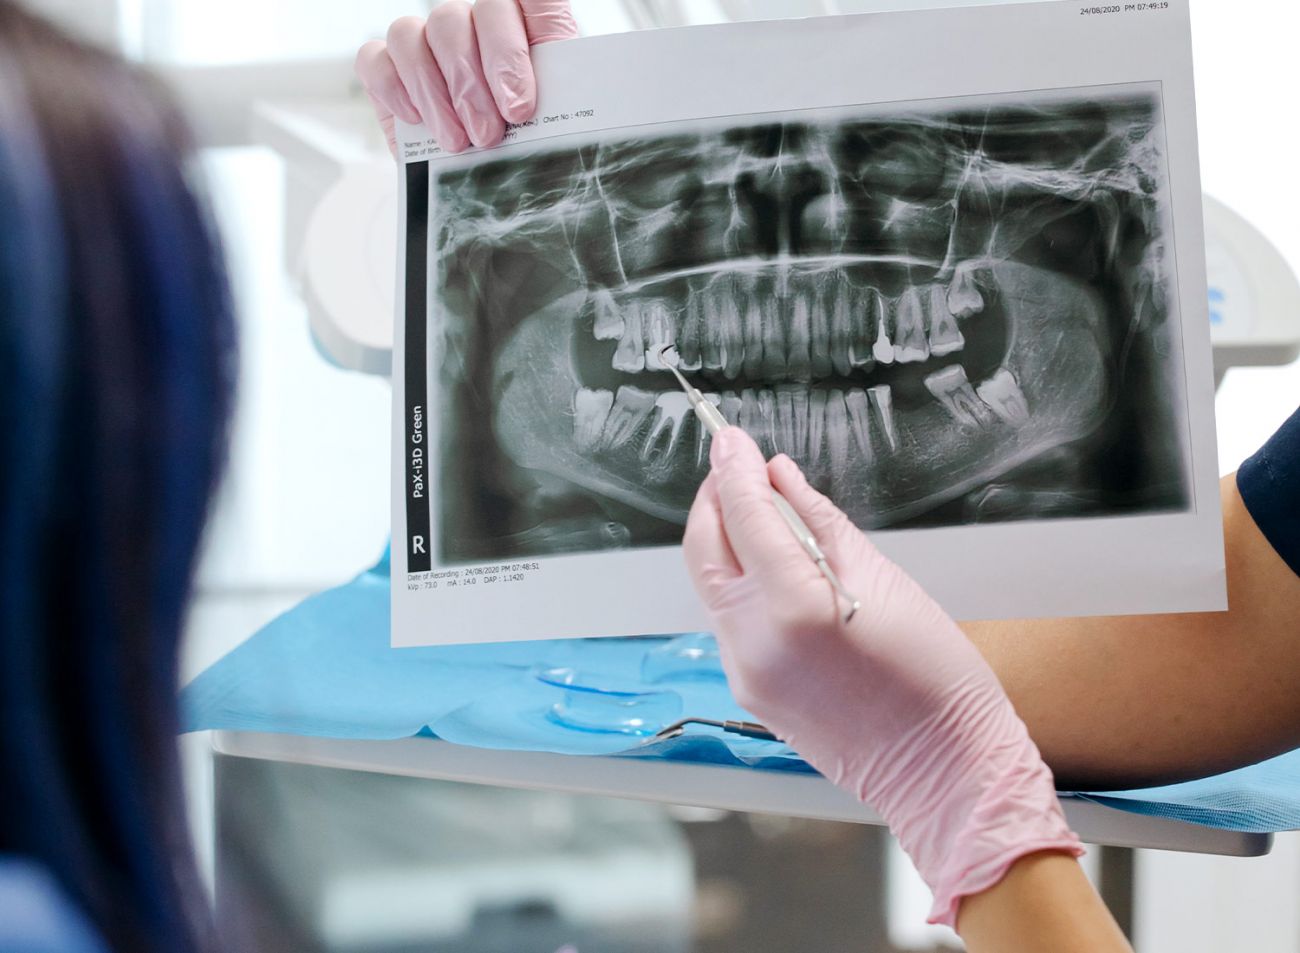

Nach aktueller röntgenologischer Untersuchung, können wir auch für Sie die bestmögliche Versorgung mit Implantaten planen!